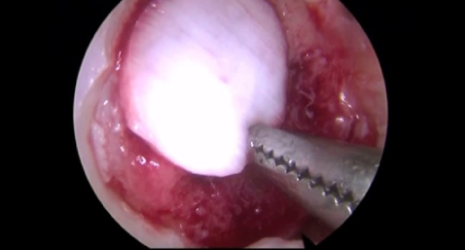

미세천공술은 관절내시경 수술을 통해 연골에 3mm 간격으로 4mm 정도의 작은 구멍들을 의도적으로 내어 출혈을 유도하고 골수를 자극하며 연골이 재생될 수 있도록 하는 치료법입니다.

□ 관절내시경을 통해 시행되어 절개가 작고 부담이 적음

□ 출혈이나 부작용이 거의 없으며 조직 손상이 적음

□ 시행 후 회복이 빠르고 통증이 적음